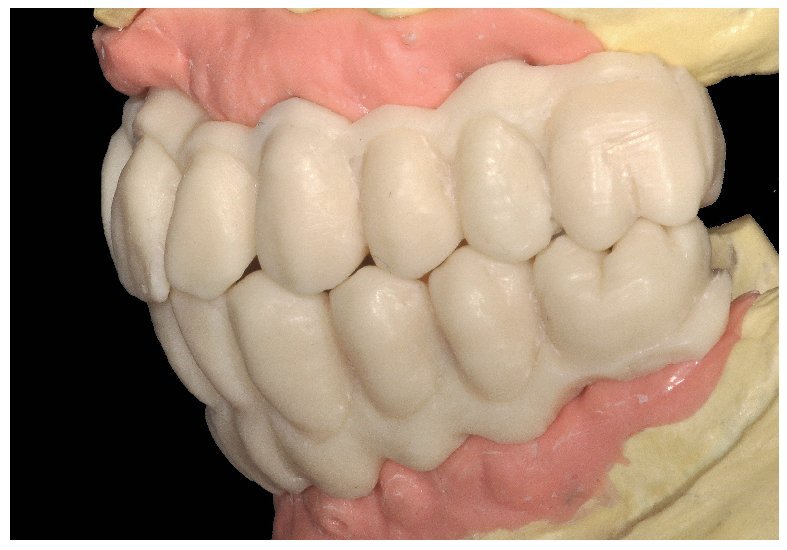

Pese a ello, es importante someter las estructuras a un control visual y mecánico, a fin de corregir eventuales discrepancias menores (figs. 99 a 102). A continuación se procede al montaje utilizando dientes protésicos prefabricados de composite (SR Phonares NHC, Ivoclar Vivadent, Ellwangen, Alemania), los cuales reproducen el tipo funcional correspondiente en virtud de sus propiedades morfológicas y estructurales y se integran armoniosamente en cuanto a su longitud dental (figs. 103 a 105). Durante la comprobación de las restauraciones protésicas, se evalúan clínica y radiológicamente ante todo la pasividad y la precisión del ajuste de la estructura. Acto seguido se lleva a cabo una comprobación de la oclusión y de la dimensión vertical, del estado de las prótesis y del tejido blando en la cresta alveolar, así como la verificación del espacio libre lingual, incluida la fonación, y el apoyo de los labios y las mejillas (figs. 106 y 107). También se debe comprobar la facilidad de higiene de la restauración de acuerdo con las habilidades manuales del paciente. A continuación se debe verificar la posición tridimensional de los dientes anteriores con los labios cerrados y durante la sonrisa, así como el aspecto global de la rehabilitación protésica.

Figs. 103 a 105. Recubrimiento estético de las estructuras con dientes protésicos prefabricados de composite. Vista frontal y lateral a derecha e izquierda.

Durante la fase de laboratorio final pueden ser necesarios diversos ajustes estéticos y funcionales. A continuación puede confeccionarse la restauración definitiva (figs. 108 a 111). Posteriormente se procede al control final mediante sendos montajes cruzados de la restauración definitiva y del modelo de planificación (figs. 112 a 115).

Figs. 108 a 111. Vista frontal y lateral de los puentes implantosoportados terminados.